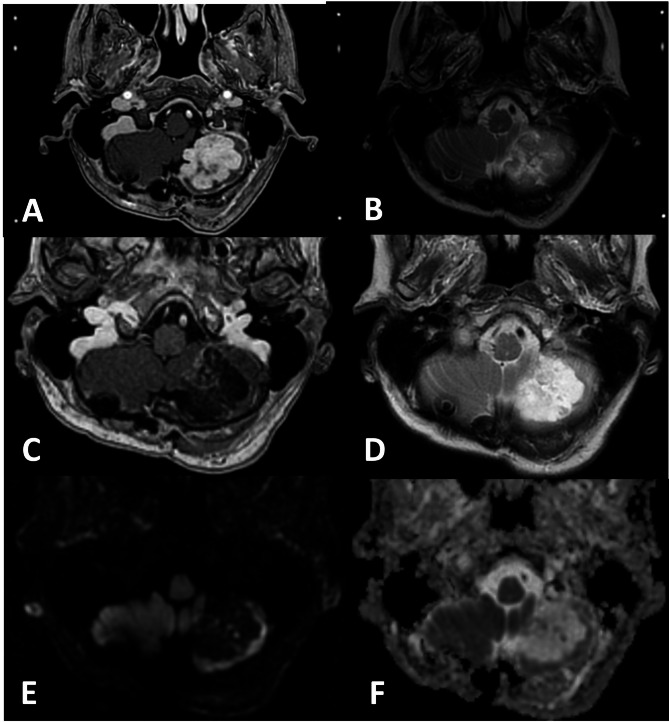

Methods: 29 patients with 35 brain metastases deemed not to be candidates for surgery, radiotherapy or systemic treatment were treated with MRI-guided adaptive Gamma Knife radiosurgery in 3 separate sessions with a 72-hour interval. Customised synchronous double-dose prescriptions were systematically utilised at each session. Estimated survival at pre-treatment was fewer than 4 weeks due to the targeted intracranial lesions. A retrospective analysis was conducted on the whole cohort, with particular emphasis on those surviving 12 months and beyond.

Results: The median overall survival was 7.3 months, with a follow-up of 7.5 years. Survival at 6, 12, 24, 36, 48 and 60 months was 62%, 41%, 17%, 14%, 10% and 7%, respectively. Local tumour control (LTC) at 1 year was 75%. 4 patients developed local recurrence late on follow-up, with a survival ranging between 12 and 40 months. 2 patients were alive at the time of submission (115- and 117-months post-treatment) with no sequelae; the remainder succumbed to general disease progression, with neurologic death being avoided throughout the whole cohort. Adverse radiation effects (ARE) were reported in 5 patients, of which 4 remained asymptomatic throughout follow-up.